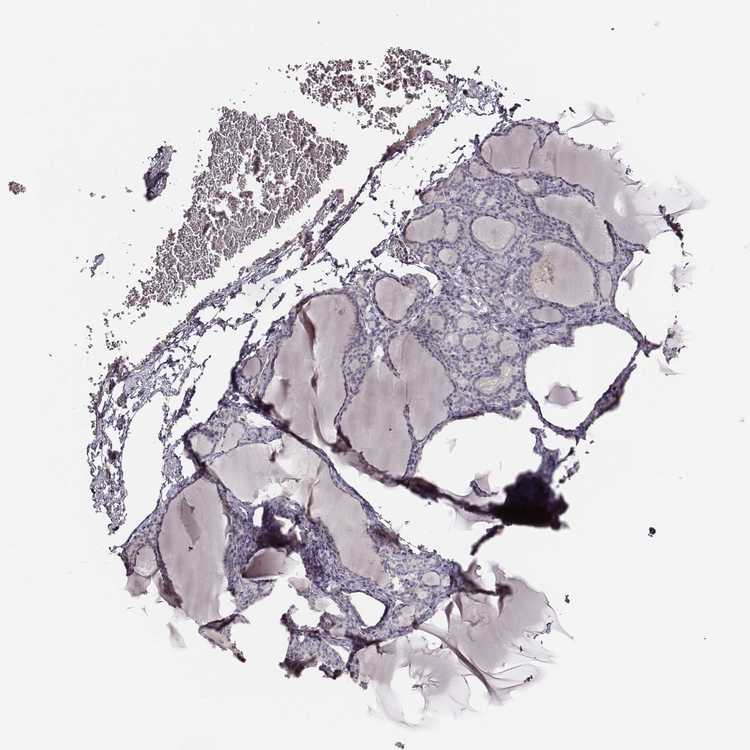

KAAG1